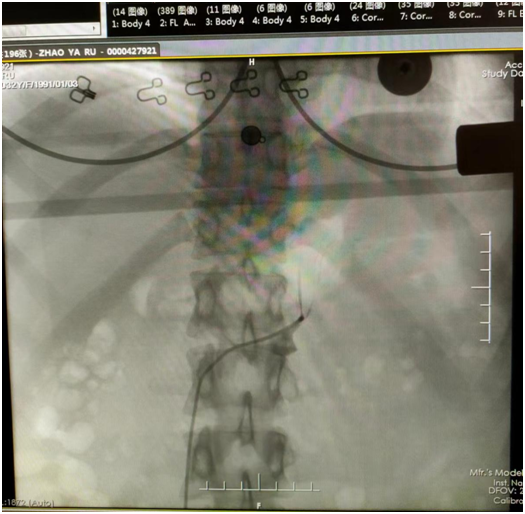

對照指南切點值顯示:卡托普利試驗后醛固酮下降率<30%,且醛固酮大于11ng/dl;輸注生理鹽水后醛固酮>10ng/dl,診斷為原醛癥。原發(fā)性醛固酮增多癥易造成難治性高血壓、心腦血管事件、腎損傷等嚴重并發(fā)癥,遠遠超過原發(fā)性高血壓引起的相關風險【1】。依據不同的臨床亞型采取手術或藥物保守治療的方式。腎上靜脈采血(AVS)是運用導管穿刺靜脈選擇性插入腎上腺靜脈后采集血樣,檢測某些指標判斷生理、病理學改變的一種介入檢查方法,主要用于鑒別原發(fā)性醛固酮增多癥的病因。目前,中國原醛癥診療的專家共識和國外原醛癥的診療指南均推薦AVS作為原醛癥功能分型診斷的金標準?;颊叻显┌Y的生化診斷標準,CT顯示不典型單側腎上腺病變,且有手術意愿,于是杭麗瑋副院長與高血壓團隊決定采用腎上腺靜脈采血的方法進行分型。

東勝區(qū)人民醫(yī)院醫(yī)院心血管內科腎上腺靜脈采血報告 |

項目 | 時間 | 醛固酮(pg/ml) | 皮質醇(ug/dl) | 選擇指數(SI) | 醛固酮/皮質醇(A/C) | 優(yōu)勢側指數(LI)及非優(yōu)勢側指數(NLI) |

右側腎上腺靜脈 | 2023.3.11 08:50 am | 1483.16 | 44.95 | 2.6 | 32.99 | LI:1.29 |

左側腎上腺靜脈 | 2023.3.11 08:30 am | 5250.66 | 206.07 | 12.28 | 25.48 | NLI:4.83 |

外周靜脈 | 2023.3.11 08:00 | 89.99 | 17.04 | / | 5.28 | / |

實驗室結果回報取血成功,并準確判斷患者為雙側分泌優(yōu)勢型。雙側優(yōu)勢分泌一般建議采用藥物治療來改善癥狀,但是目前研究顯示手術可能為患者帶來更大的獲益。螺內酯(MRA)是一線用藥,可以有效地降低醛固酮水平,但該藥對醛固酮的拮抗是非選擇性的,有報道MRA的副作用發(fā)生率高達50%,如導致高血鉀、胃腸道反應、男性乳房發(fā)育及性功能減退、女性月經紊亂、乳腺刺痛及中樞神經癥狀等,因此年輕人可能不太愿意接受【2】。其次,研究顯示藥物治療與手術治療對于患者遠期預后來說,手術可降低中遠期心血管死亡率【3】。但是手術僅適用于醛固酮腺瘤、單側腎上腺皮質結節(jié)增生、醛固酮癌的患者,而不適用于雙側腎上腺增生(特醛癥)、單側醛固酮腺瘤伴有對側腎上腺增生、家族性醛固酮增多癥。對于不想接受藥物治療又不想行手術治療的患者,腎上腺動脈栓塞術是一種有效的替代治療方法。超選擇性腎上腺動脈栓塞術是通過導管將化學消融劑超選擇地注入腎上腺動脈,直接選擇性毀壞腎上腺組織,阻斷醛固酮產生的微創(chuàng)治療方法,與傳統手術切除或經腹腔鏡手術切除比較,具有微創(chuàng)、并發(fā)癥發(fā)生率低、住院時間短、費用低的優(yōu)勢【4-5】。其三有研究顯示無水乙醇隨血流分布對彌漫生長的分泌醛固酮的微結節(jié)或細胞簇進行損毀,相當于腎上腺部分切除,術后沒有出現腎上腺皮質激素水平降低,也無腎上腺皮質功能減退現象【6】。杭麗瑋教授綜合考量,通過與家屬充分溝通,擬對左側腎上腺采用超選擇性腎上腺動脈栓塞術。